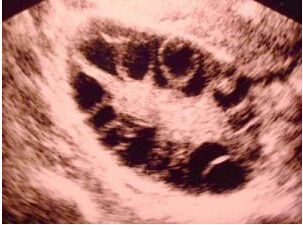

我们具体来了解一下多囊卵巢综合征(pcos)超声表现:

1、双侧卵巢增大,可为正常的2-3倍,主要是厚度增加,较大径线可达50mm。

2、卵泡包膜增厚,声像图显示卵巢轮廓清晰,表面回声增强,周围可出现一薄强回声环。

3、经阴道超声卵巢内可见到≥12个卵泡(经腹≥10个卵泡),直径在2-8mm。

4、髓质水肿,表现为卵巢中央髓质部见一强回声区。正常情况下声像图不显示卵巢髓质回声。